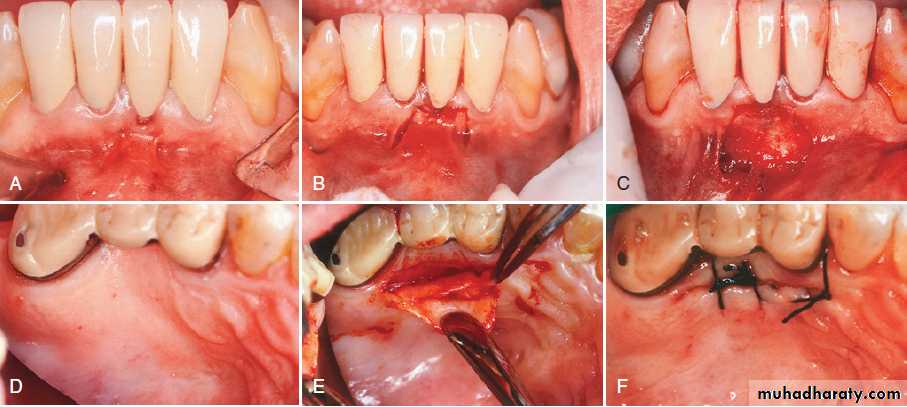

Pouch and tunnel technique for root coverage. (A) Preoperative view, showing gingival recession. (B) A sulcular incision is made from the mesial to the facial line angles. (C) A tunnel is made through the papilla using a blunt incision. (D) A connective tissue graft is taken from the palate. (E) The connective tissue is placed through the papillary tunnel and apically beneath the pouch. (F) The facial gingival margin covers the connective tissue using horizontal mattress sutures interdentally. (G) Postoperative view, showing complete root coverage and a thickened gingival margin at 3 months.